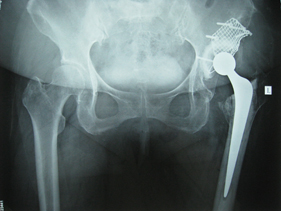

rivision total hip replacement for dislocation and severe bone defect

(pre-op) rivision total hip replacement for dislocation and severe bone defect

anterior-posterior view of bilateral hips